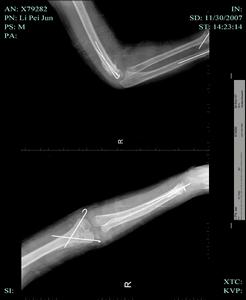

3、X線檢查

除正、側位X線攝片外,尚應根據傷情拍攝特殊體位相,如開口位(上頸椎損傷)、動力性側位(頸椎)、軸位(舟狀骨、跟骨等)和切線位(髕骨)等。複雜的骨盆骨折或疑有椎管內骨折者,尚應酌情行體層片或CT檢查。

無移位者用上肢石膏或石膏托功能位固定,有移位者經復位後達到或近於解剖復位者,

![]() | ![]() |